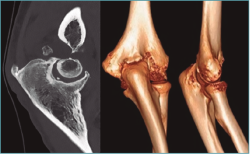

Las pruebas de imagen más útiles en este contexto son la radiografía simple (Figura 3) y la tomografía computarizada (TC) (Figuras 4 y 5), que evalúan la congruencia de las superficies articulares, la presencia de osteofitos u osificación ectópica, o alteraciones de la alineación ósea. Además, se evaluará la consolidación de fracturas previas, si es el caso, o la posible implicación del material de osteosíntesis en la falta de movilidad (si está correctamente situado, no tiene por qué interferir con la movilidad del codo)(6).

Figura 5. Reconstrucción sagital y tridimensional de una malunión de húmero distal, con alteración de la alineación de la superficie articular en extensión y malrotación interna, que condiciona una pérdida de flexión, como ejemplo de rigidez intrínseca.